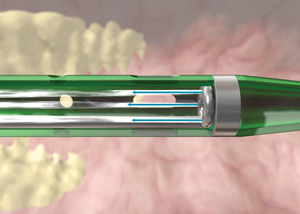

O Sistema de Trombectomia AngioJet permite a remoção percutânea de trombos

localizadas em artérias e veias periféricas, pontes de safena, artérias coronárias e condutos de acesso AV nativos ou sintéticos. A trombectomia é realizado com jatos de solução salina de alta pressão contidos na haste do cateter. O jatos de solução salina criam um efeito de baixa pressão para atrair o trombo para o cateter, fragmentar

o trombo e remova o trombo do local de tratamento. O sistema consiste de um conjunto de trombectomia de uso único (vários modelos disponíveis) e um consola móvel.

Mecanismo de Ação

1. O Console AngioJEt monitora e controla o sistema.

2. O Console energiza a bomba, que envia solução fisiológica pressurizada para a ponta do cateter.

3. Os jatos de solução fisiológica viajam para trás para criar uma zona de baixa pressão causando um efeito de vácuo. (Imagem 1)